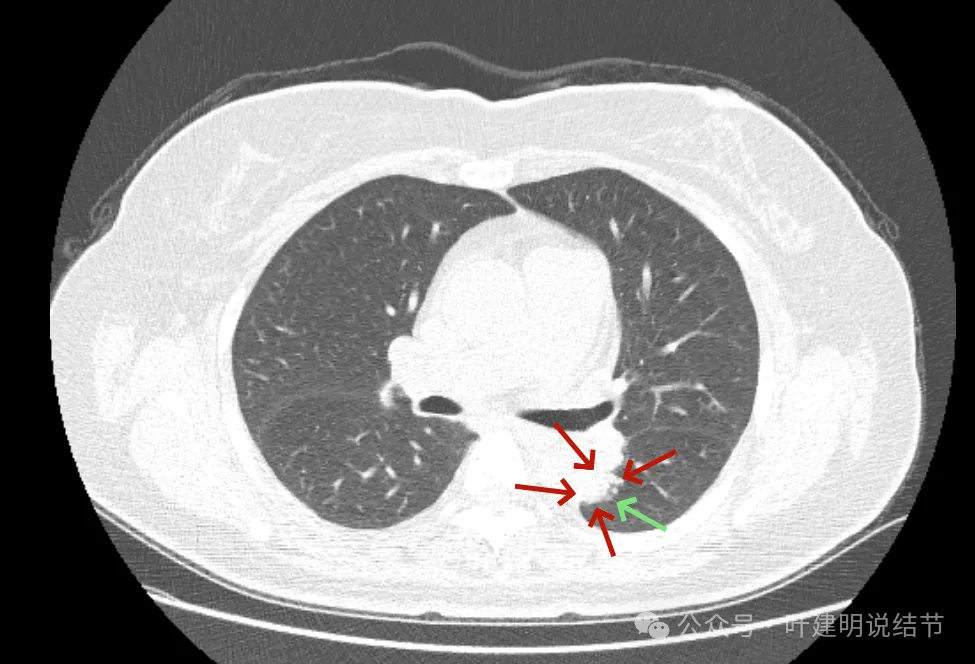

最后看2024年复查的影像:

病灶出现,密度不纯,毛刺细长。

轮廓稍显模糊,密度不均,毛刺偏长。

病灶膨胀感较之前明显;与主动脉壁之间缝隙不太明显了。

实性成分似乎较前增多,胸膜略有牵拉。

膨胀性较前明显,基本实性。

与主动脉壁贴得紧了,但褐色所指处边缘还是较为平直。

与主动脉壁之间紧贴了,对侧出现了细毛刺,整体基本都是实性密度了。

实性成分占比增加,邻近结构受压,边缘毛刺出现。

表面不平,密度高,与主动脉间隙消失。

现在较2年前有进展,显示了更多的恶性影像特征,整体密度也增加,膨胀性也明显起来,并对邻近结构有压迫,表面不平毛糙。持续存在的实性为主的结节随访进展,并显示出更多恶性特征,那就得高度怀疑恶性,而且不宜再随访了。